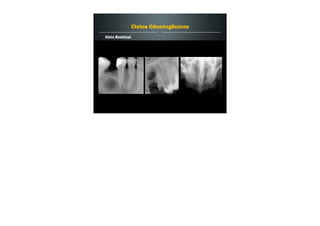

Cisto Ósseo Simples / Cisto Ósseo Traumático

Cavidade benigna, vazia ou contendo liquido dentro do osso,

desprovida de revestimento epitelial.

Etiologia desconhecida - trauma.

Pode acometer qualquer osso do corpo, mais frequente nos

osso gnáticos.

10 à 20 anos de idade.

Restrito a mandíbula.

Assintomático e tende a regredir com o avanço da idade.

Pseudocistos

Radiograficamente:

Defeito radiolúcido bem delimitado.

Enluvamento - efeito de cúpula nas raízes dentárias.

Dentes vitais.

Não causa expansão de corticais nem deslocamento de

estruturas adjacentes.